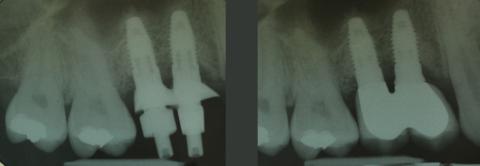

MehrDentale Implantate zum Ersatz parodontal geschädigter Zähne im Oberkieferseitenzahnbereich

Eine mögliche Vorgehensweise anhand einer Falldarstellung mit Recall über 14 Jahre